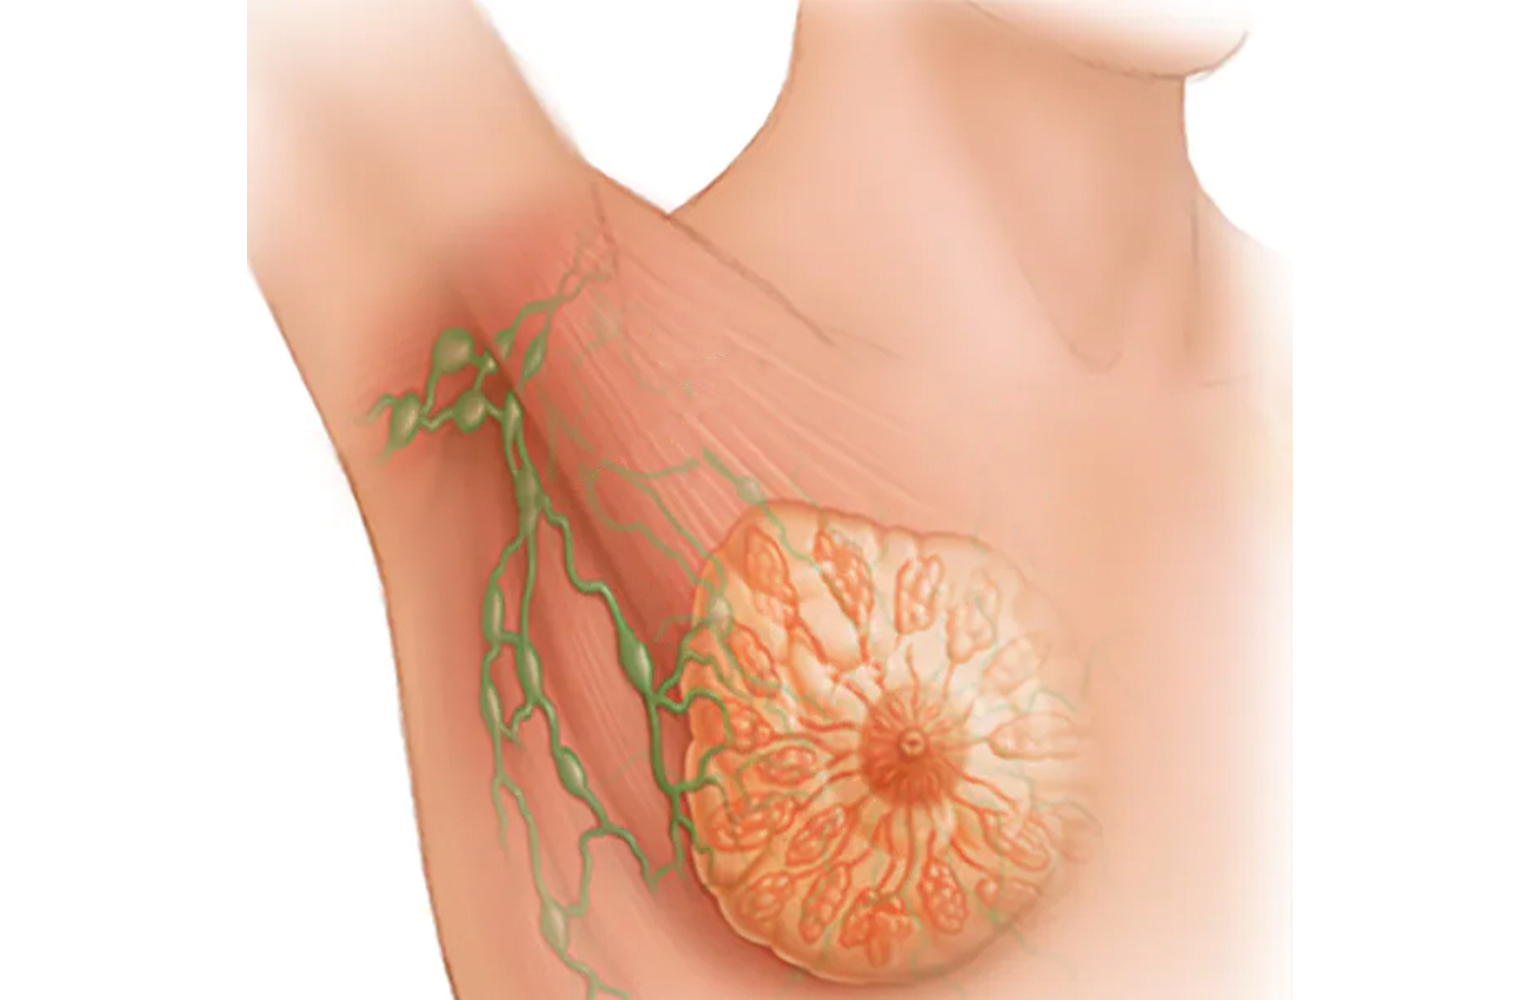

Detaylı BilgiMeme Kanseri

Meme kanseri, meme dokusunu oluşturan hücre gruplarından birinin değişime uğraması ve kontrolsüz olarak çoğalması nedeniyle oluşmaktadır.